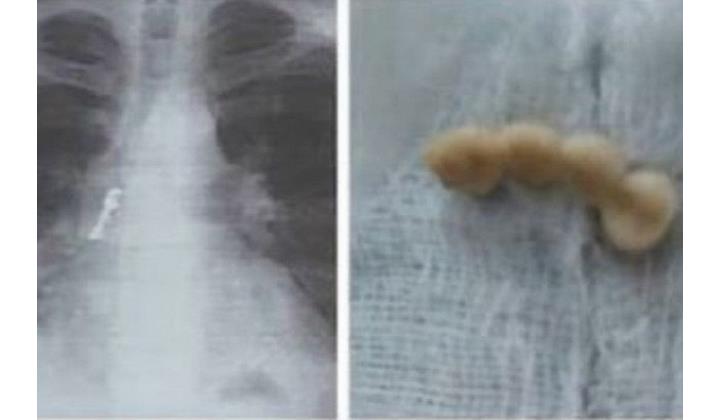

Пешекарри ахтармишунар тухвайдалай кьулухъ тайин хьайивал, сухварин “муьгъ” чапла патан жигерда акIанвай. Идакди жигердиз са кьадар зиянни хьанвай. Эгер агьали вахтунда больницадиз атаначиртIа, стIалжем, жигерда ирин кIватI хьун мумкин тир.

Операциядин нетижада духтурри сухварин “муьгъ” ахкъудна. Алай вахтунда итимдин сагъламвал хъсан хьанва.